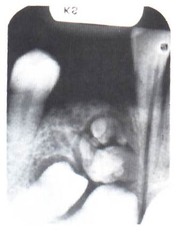

-young adult -well defined unilocular radiolucency around crown of unerupted impacted or developing tooth